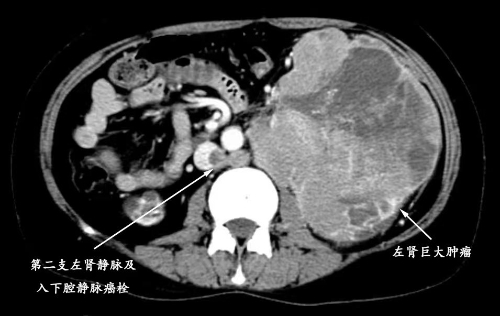

邵远主任仔细阅片后,决定将患者收治入我院嘉定院区泌尿外科病房进行术前评估,同时在肾内科协助下规律透析治疗。我院检查发现,但女士肿物起源于左侧肾脏,体积达11*12.8*11.3cm,几乎填充整个左侧腹部(达T4期),推挤脾胃及同侧肠管。不仅如此,患者有两支左肾静脉,其主干及下腔静脉内均存在长段癌栓(将近Mayo Ⅲ级),一旦癌栓脱落,后果不堪设想。